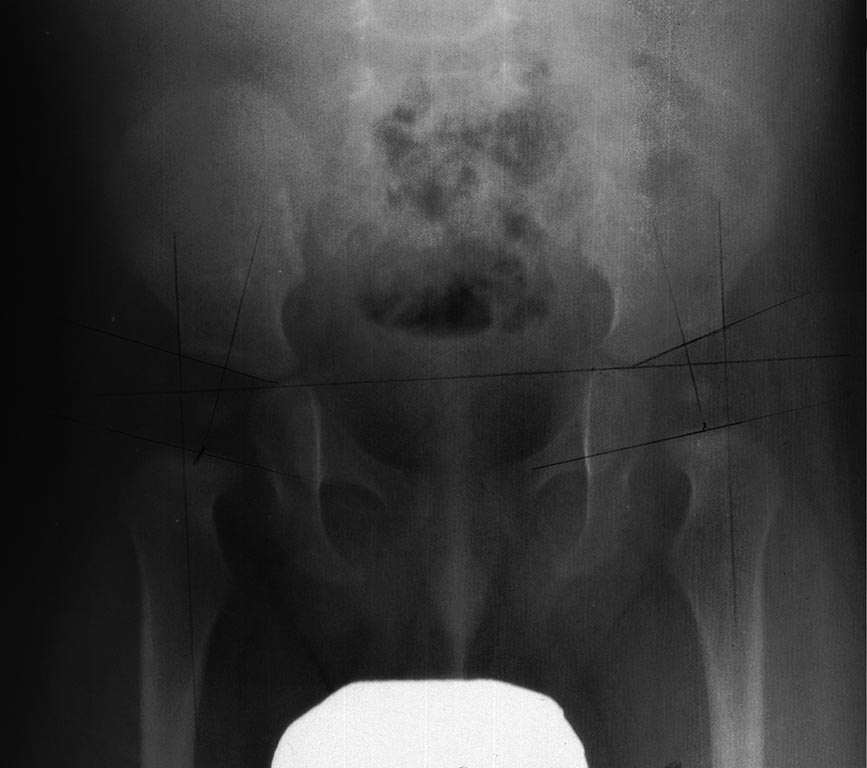

Уважаемые господа!Прошу Вас оказать консультацию по вопросу возможной дисплазии ТБС у ребенка. Моему сыну 7,5 месяцев. Наблюдение у всех врачей проходим с рождения по графику. В роддоме никаких отклонений не было выявлено. В месяц был пройден осмотр ортопеда и сделано узи тбс. Узи прилагаю. Отклонений не выявлено. Невролог и хирург также дали заключение: здоров, развит по возрасту. В три месяца также прошли осмотр невролога и хирурга.вновь все в порядке. В 4,5 месяца вновь сделали узи для подтверждения формирования ядер окостенения головок тбс. Заключение узи: все в норме. Узи прилагаю. В 6 месяцев (конец октября 2015 г) прошли осмотр невролога и хирурга. Заключение: здоров. Ортопед в поликлинике настоял на рентген-снимке тбс, мотивируя тем, что узи и осмотр непоказательны. 25/11/15 сделали рентген-снимок тбс. Скан снимка прилагаю. Заключение рентгенолога : 1) покрытие головки бедра крышей вертлужной впадины достаточное 2) ядра окостенения головок бедренных костей - развиты по возрасту. Д=5.3) ацетабулярные углы - с обеих сторон 20 градусов. 4) децентрация головки бедренной кости - определяется.Дополнительные критерии: линия шентона несколько растянута, с уступами. Заключение: косвенные R-признаки дисплазии тб суставов. Дополнительно к анамнезу выше: Стоять ребенок в кроватке с опорой сам стал с 5 месяцев. С шести стал уверенно ходить с опорой по кроватке. Мы этого не поощряли и не помогали. Но и не удерживали. Часто когда он возбужден, то начинает в кроватке, стоя и держась за перила прыгать сильно на месте. Делает так довольно часто. Может это провоцирует смещение? Более никаких отклонений до сих пор у ребенка не выявлялось.Также с данным снимком были у ортопеда. Он также обнаружил дисплазию. Его дивгноз звучит так: дисплазия ТБС с умеренной задержкой окостенения головки левого бедра и умеренной децентрацией головок бедер. Вальгусная установка стоп.Прошу вас ответить на следующие вопросы :1) какие выводы можно сделать по представленному снимку? Согласны ли вы с заключением рентгенолога? 2) действительно ли так непоказательны узи и осмотр? Они могут пропустить патологию? Тем более что рентген делают только при выявления отклонений на узи или осмотре. 3) необходимо ли принимать обязательно витамин д3? Если да то в какой дозе и какова его роль в лечении/профилактике дтбс? Заранее благодарю за помощь.

На снимке никаких проблем не видно.